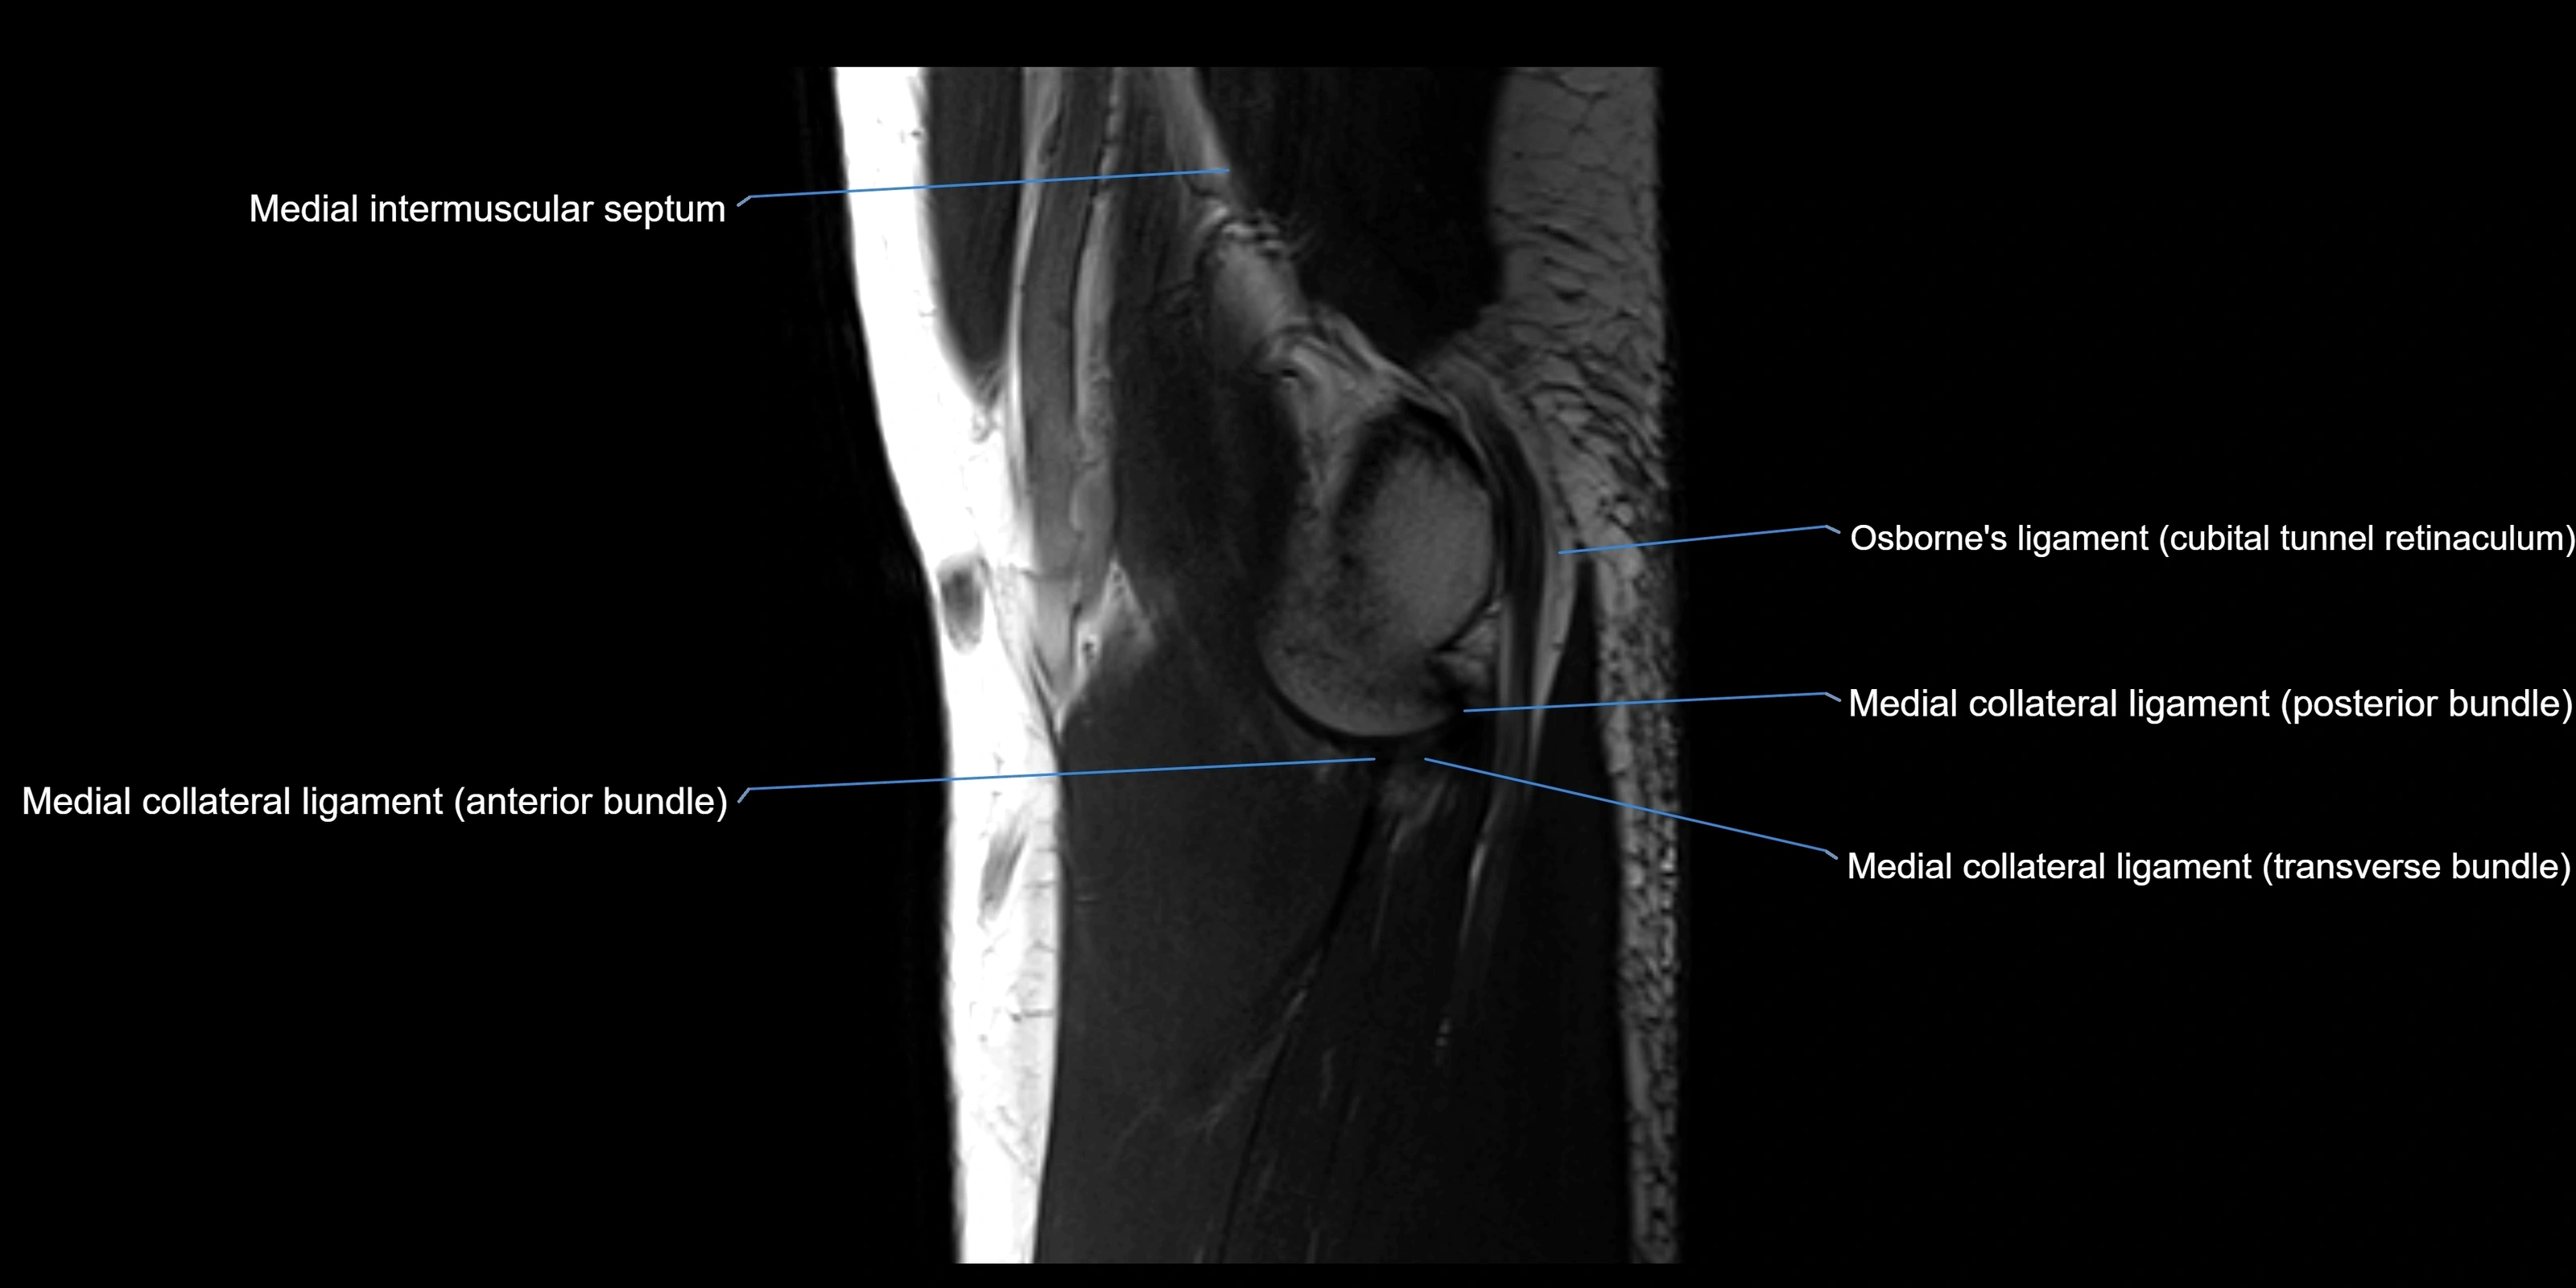

MRI images

image